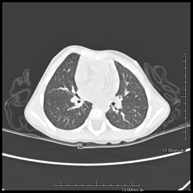

- TC Tórax

Prueba diagnóstica que consiste en obtener imágenes del tórax de alta definición anatómica (pulmones, corazón, mediastino, grandes vasos, caja torácica, etc.) mediante el empleo de un equipo de TC (Tomografía Computarizada). Dichas imágenes se estudian posteriormente en una estación de trabajo que permite reconstrucciones bidimendionales en diferentes planos del espacio y también reconstrucciones 3D (volumétricas). Algunos estudios requieren el empleo de contraste yodado para mejorar la definición de las imágenes.

Prueba diagnóstica que consiste en obtener imágenes del tórax de alta definición anatómica (pulmones, corazón, mediastino, grades vasos, caja torácica, etc.) mediante el empleo de un equipo de TC (Tomografía Computarizada). Dichas imágenes se estudian posteriormente en una estación de trabajo que permite reconstrucciones bidimendionales en diferentes planos del espacio, y también reconstrucciones tridimensionales (3D: volumétricas). Algunos estudios requieren el empleo de contraste yodado para mejorar la definición de las imágenes.